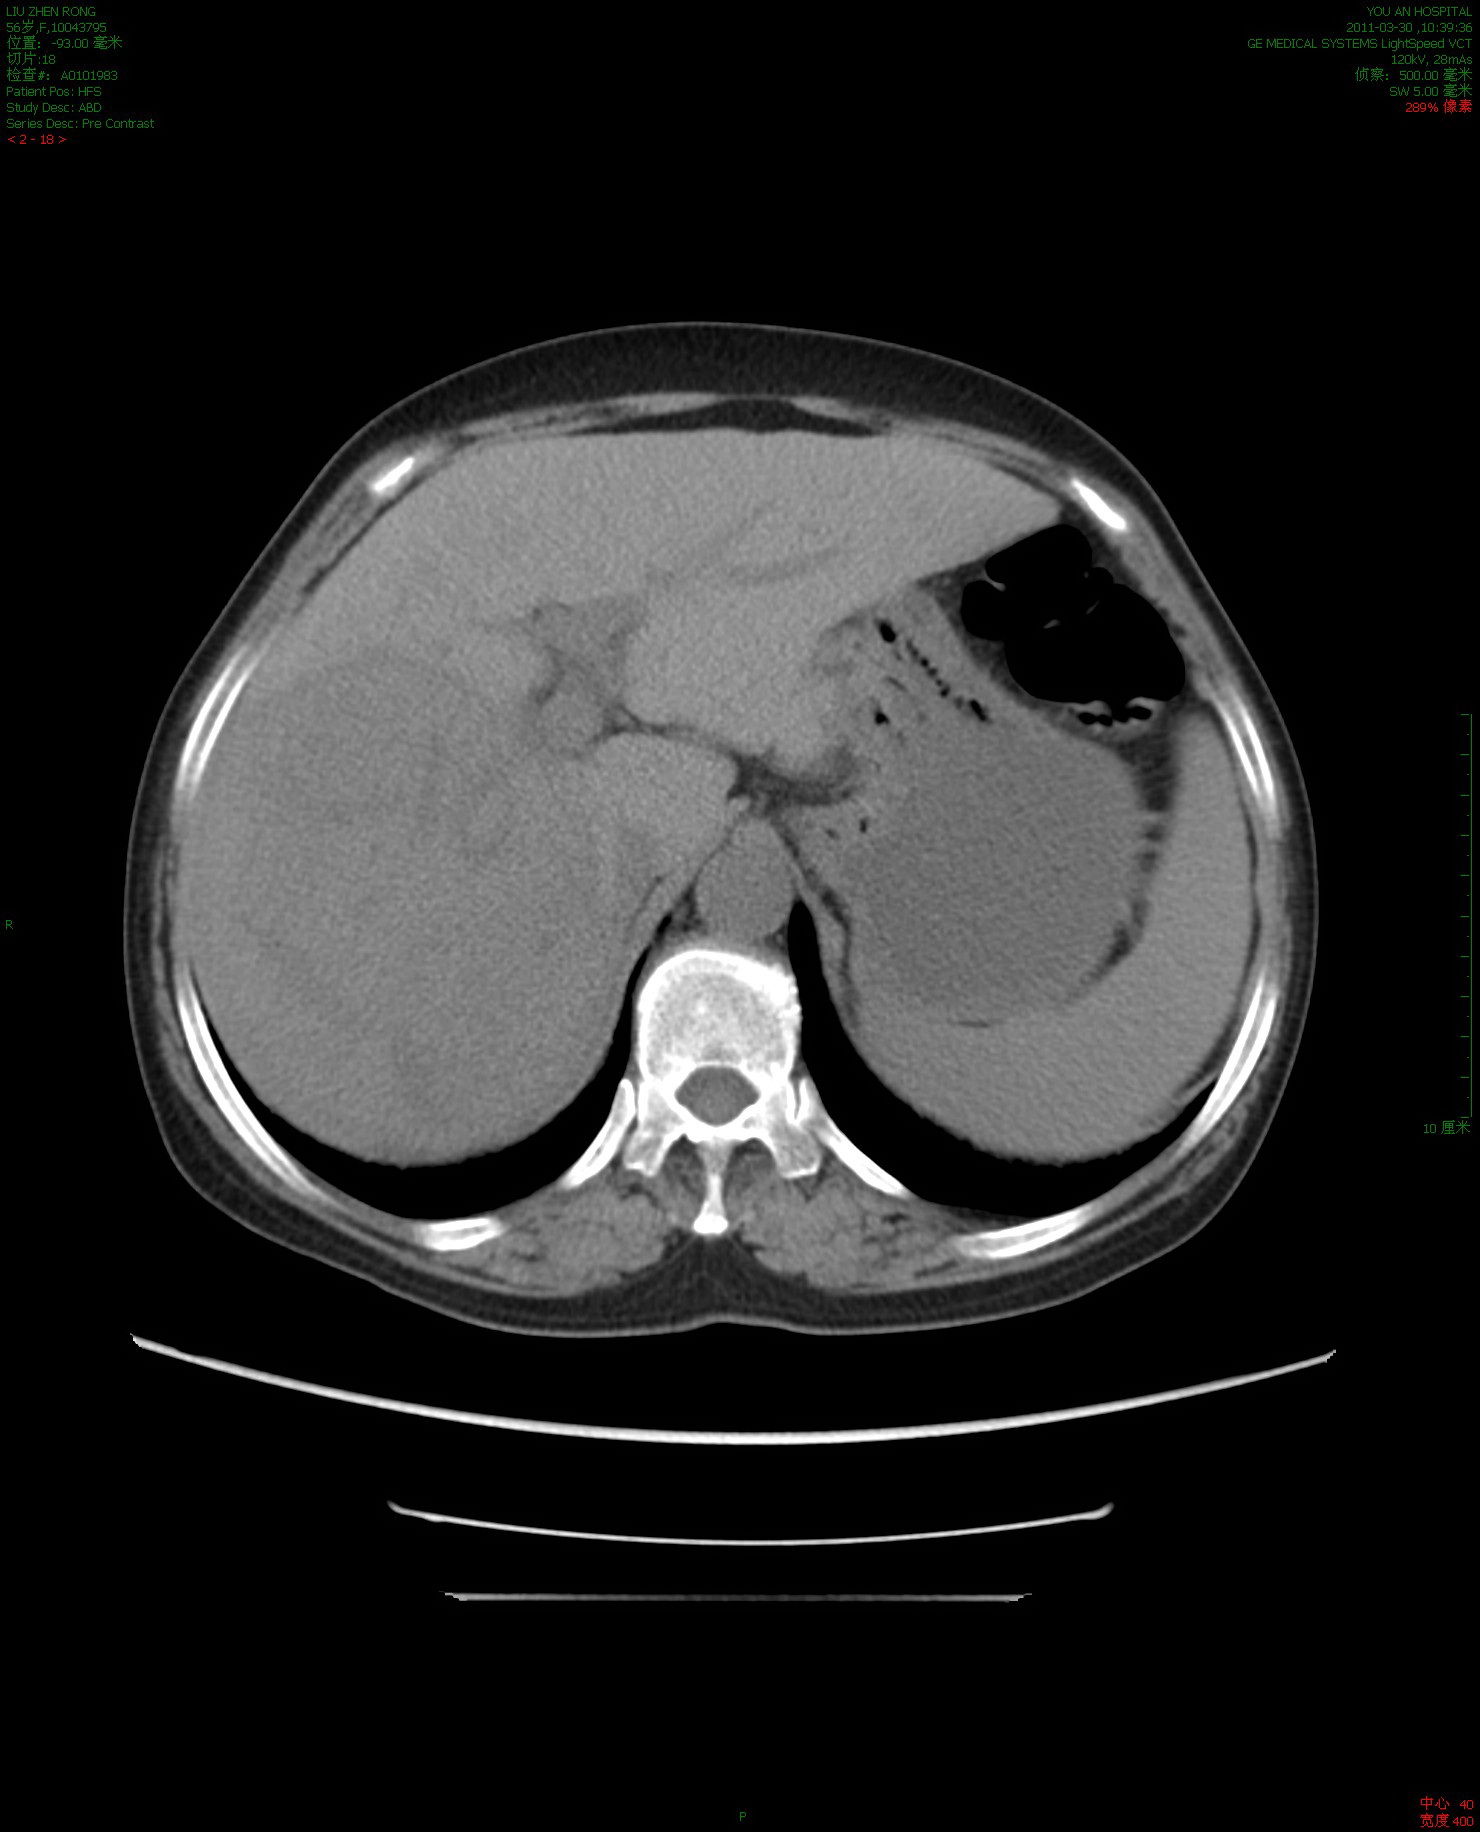

消融肿瘤40%-50%微创治疗前增强ct56岁的肝癌晚期患者,女性

图片尺寸1480x1832